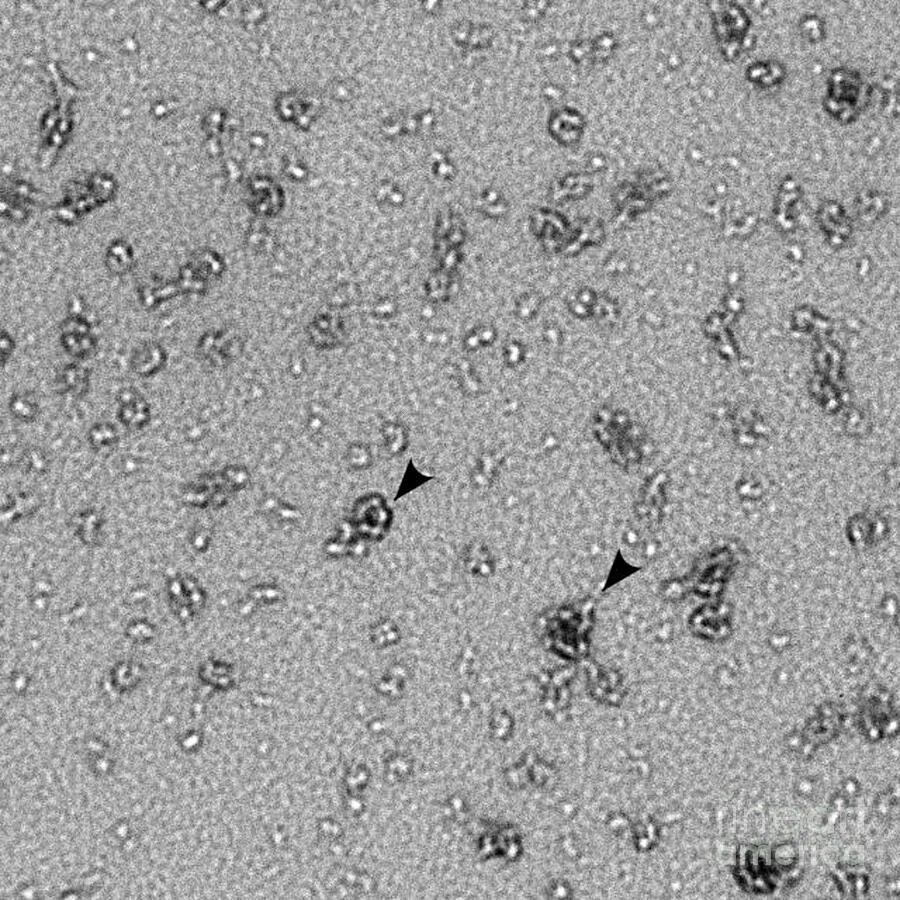

Хламидии под микроскопом